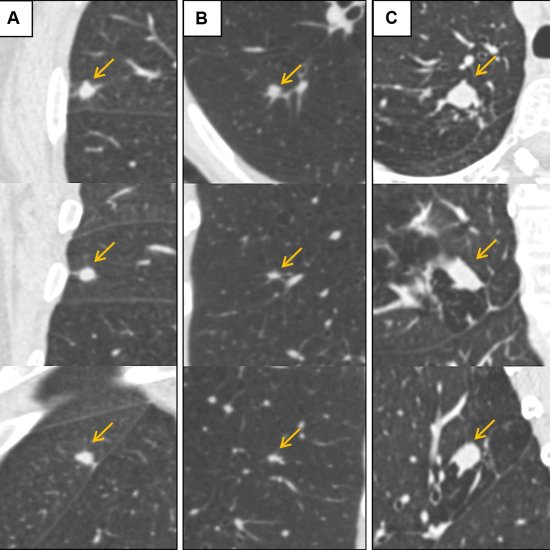

News • Estimation of nodule malignancy risk

Misinterpreting the malignancy risk of lung nodules often results in high false-positive rates, unnecessary follow-ups, increased patient anxiety and healthcare costs. A new study suggests that AI can fix this. |